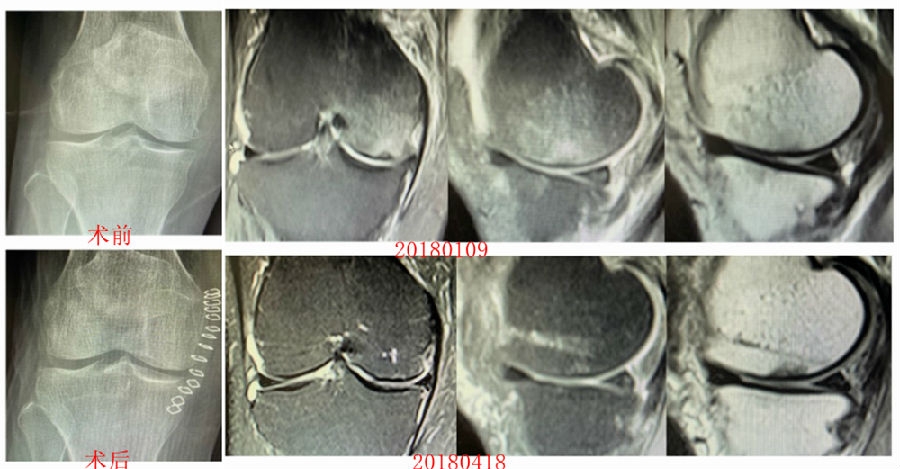

病例2:女,69岁,主诉左膝关节内侧疼痛1月余。2017年11月X光见右膝股骨髁负重区的软骨下区域出现了椭圆形透亮影,MR检查见股骨内侧髁骨坏死,合并内侧半月板外突和后角层裂,半月板相对突出百分比(RPE)25.32%,矢状位病变区域前后径为23.96mm,关节线会聚角6°。

予克氏针钻减压,消炎止痛药物口服、静滴唑来膦酸钠注射液,避免负重6周,后改部分负重至3个月,患者依从性差。2018年1月复查MR见骨髓水肿少许吸收,坏死区扩大,半月板相对突出百分比(RPE)33.53%,矢状位病变区域前后径为26.89mm,患者仍有膝关节疼痛症状,建议行手术治疗,患者拒绝手术后失访。